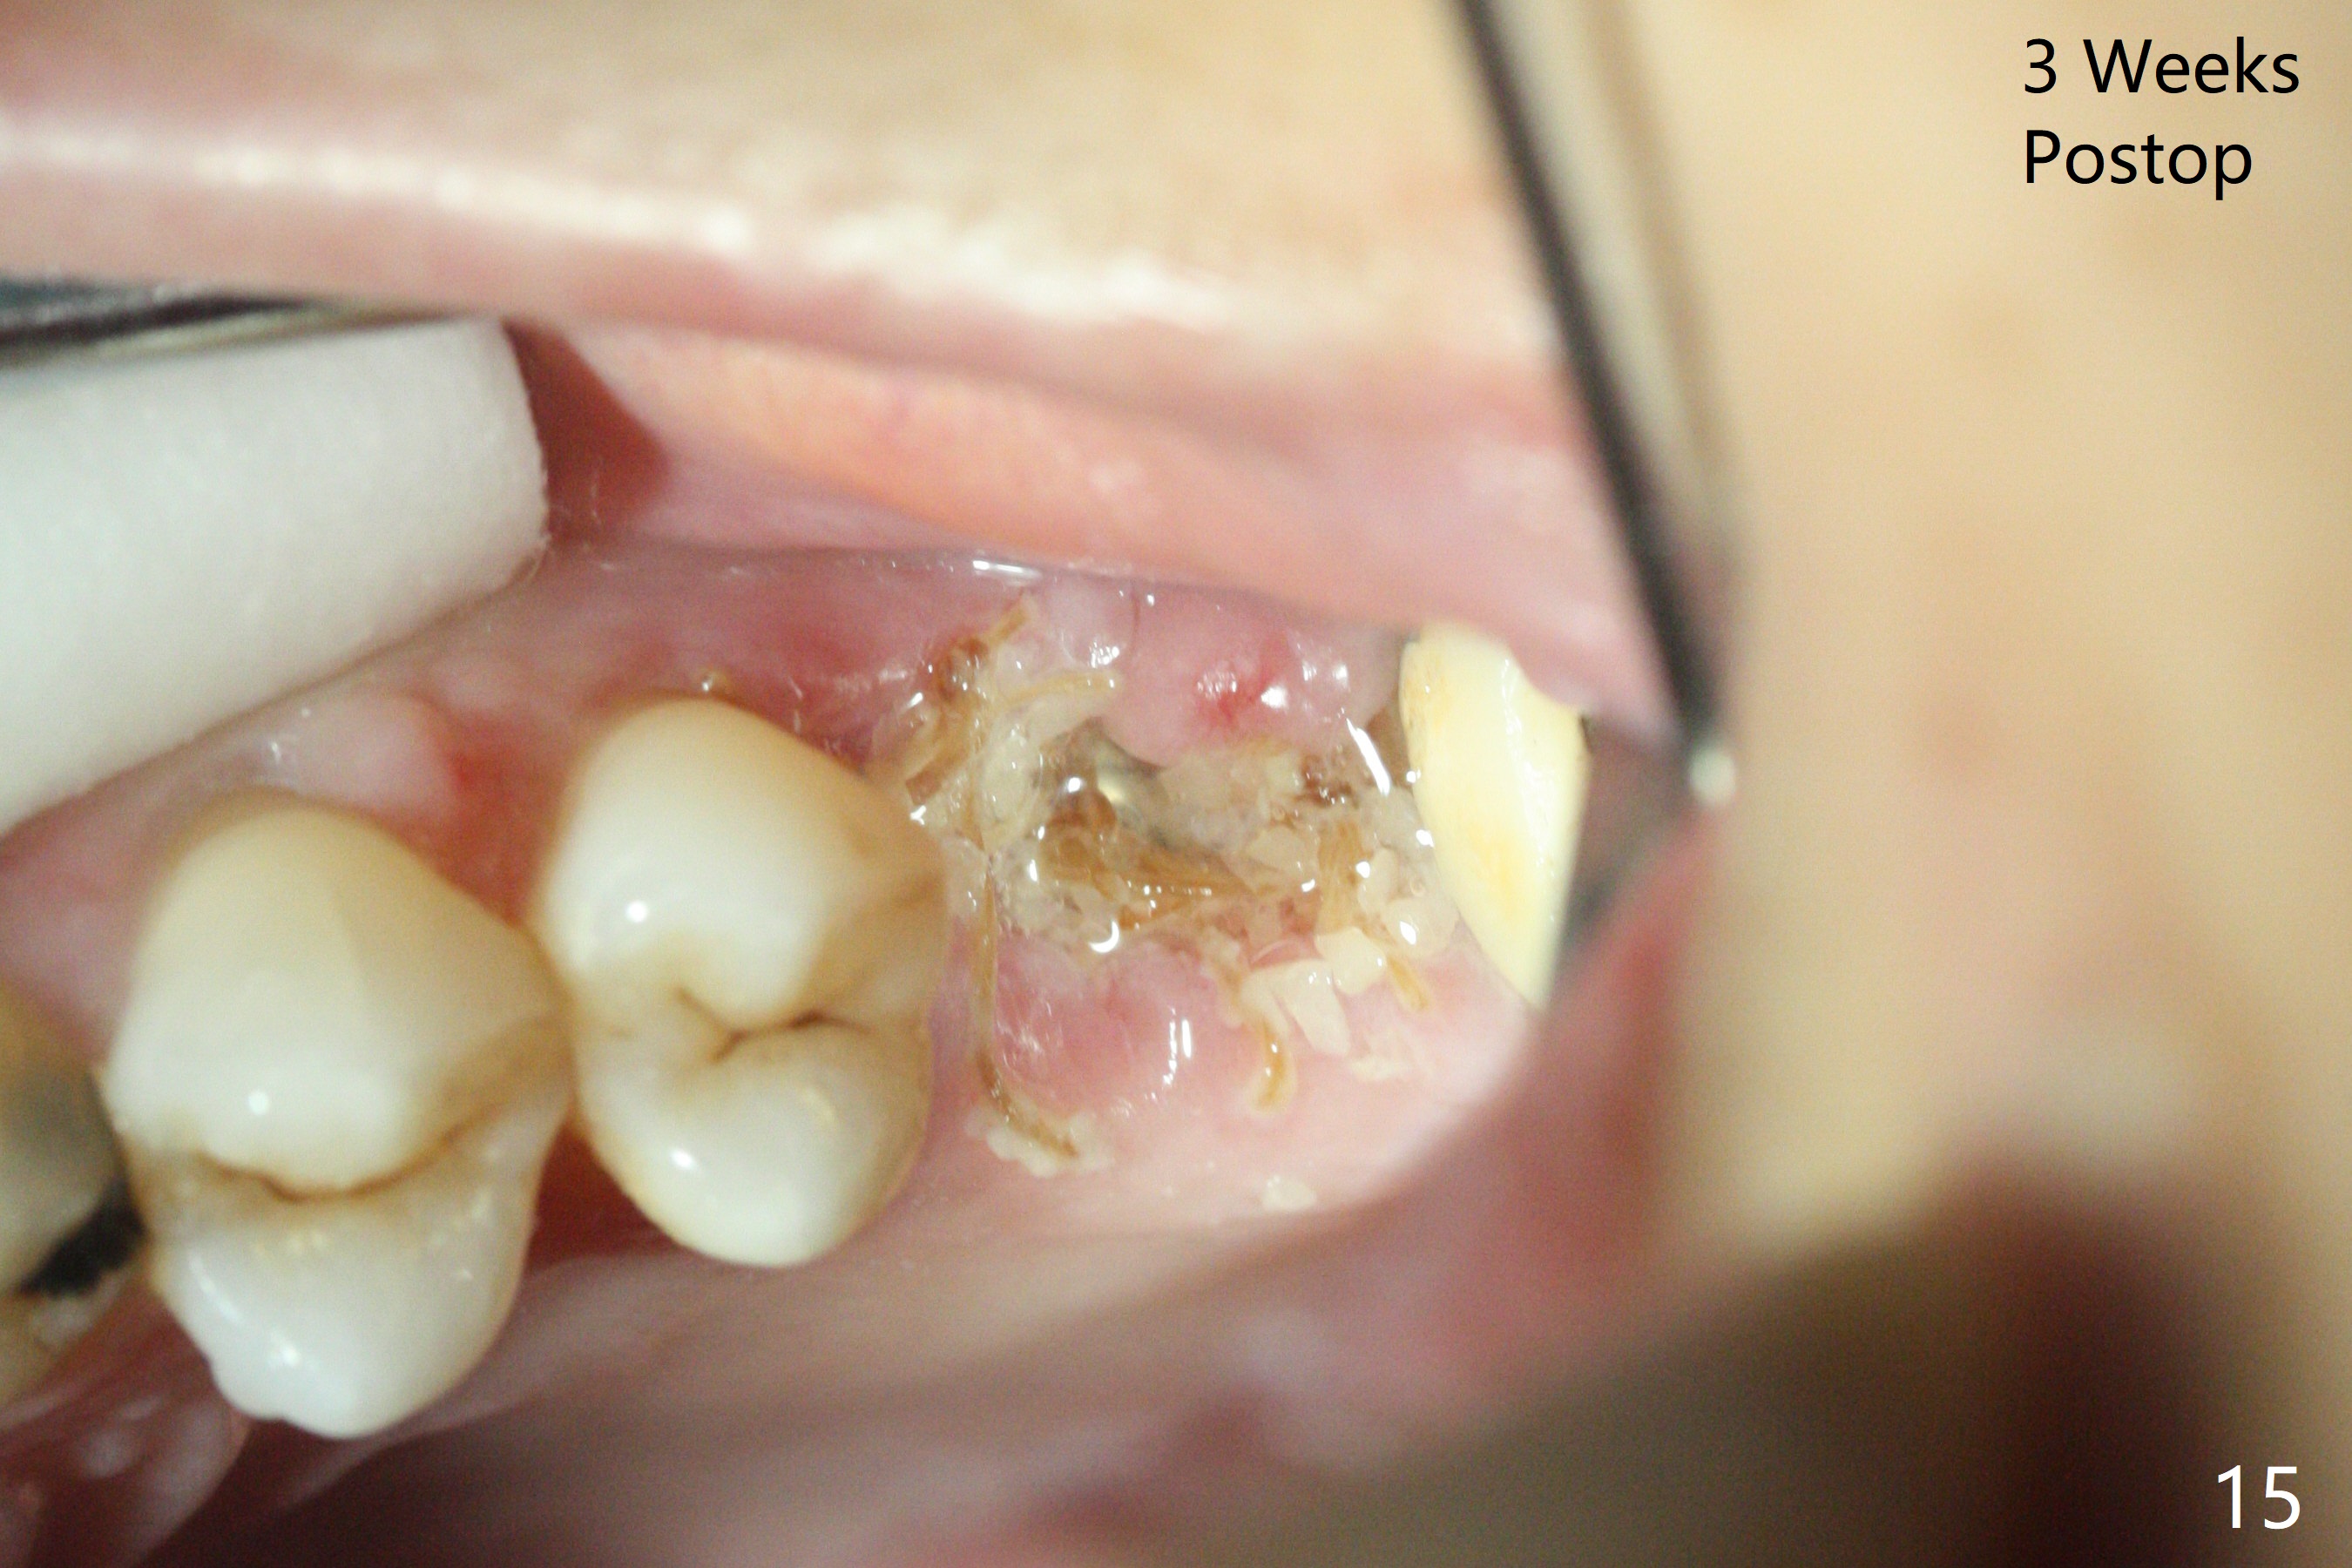

A 57-year-old woman complains of bad smell while use of water flosser between 11 and 21 months post cementation of implant crown at #14 (Fig.1,2). Bone loss is more obvious with CBCT (Fig.3,4), in spite of apparently normal gingiva around the implant after removal of the abutment and crown (Fig.5). In fact the buccal (B) gingiva is fragile with easy access to the underlying implant plateau. Following flap elevation, the bone loss is evident (Fig.6), but the implant plateau is slightly subcrestal (Fig.7 *). The exposed implant threads are covered with the 1st round of bone graft (Fig.8). After 2nd round of allograft (Fig.10-12) and collagen membrane, the flaps are approximated (Fig.9). The wound is covered by acrylic dressing. The latter is loose, but stays in place 1 week postop (Fig.13). Due to short neighboring teeth, the acrylic dressing is able to be removed with wiggling; it appears that the wound is healing (Fig.14). The dressing returns for another 2 weeks; some of the graft has been lost (Fig.15). The dressing does not return 7 weeks postop, since the wound is healing (Fig.16).